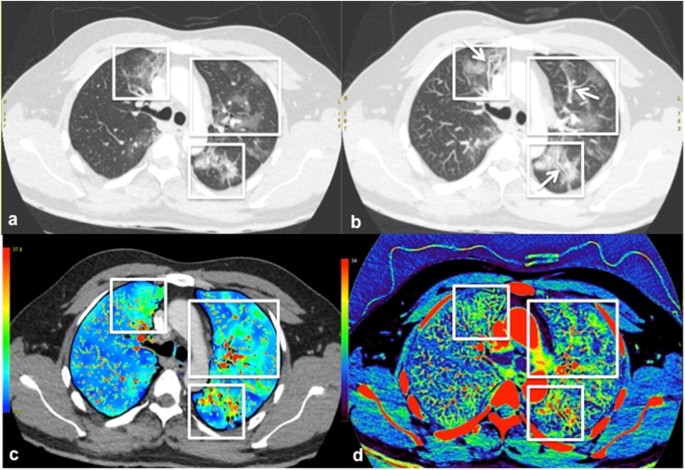

a Axial image of the lung bases show a focal consolidation with peripheral ground glass opacity in the posterobasal left lower lobe (black arrow). Subtle ground glass opacities are also visible more medially in the left lower lobe and the basal right lower lobe (white frames). b Corresponding perfusion blood volume (PBV) image shows considerably increased perfusion in the left lower lobe (black arrow). A few areas of mild hypervascularity are also recognizable in the rest of the lung bases with subtle ground glass change (white frames)

a, b Axial image of the upper lungs and corresponding maximum intensity projection (MIP) image demonstrate scattered ground glass opacities bilaterally (white frames), with abnormally dilated subsegmental vessels in some of the central and peripheral opacities at contiguous slices (white arrows). c PBV image at the same level shows regional areas of increased perfusion corresponding to the ground glass opacities (white frames). d Corresponding iodine map image also demonstrates hyperperfusion as well as segmental and subsegmental vasodilatation, especially at the medial aspect of right upper lobe and the apical segment of the left lower lobe (white frames)